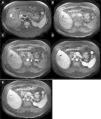

HHs are suspected when ultrasonography shows nodules with homogeneous hyperechogenicity, but additional imaging tests, usually triphasic computed tomography (TCT) or magnetic resonance imaging (MRI), are required to confirm the diagnosis due to the lack of specificity of ultrasonographic findings. TCT typically reveals progressive enhancement during the arterial phase in a centripetal fashion. MRI shows a low signal intensity on T1-weighted images, high signal intensity on T2-weighted sequences, and an inward enhancement after gadolinium administration can be seen.14 Tc-99m-labeled red blood cell single emission photon computed tomography may be helpful when there is diagnostic uncertainty; it has sensitivity, specificity and accuracy of 97%, 83%, and 96%, respectively.15 Positron emission tomography is useful to differentiate heterogeneous HH from angiosarcomas.16 The differential diagnosis includes angiomatosis, metastases, hematic cyst, hepatic peliosis, and hepatocellular carcinoma, among others.

MethodsWe performed a retrospective analysis of patients with HH at our hospital within the time frame of January 1, 1990 and November 31, 2008. We made an electronic search regarding outpatient and inpatient hospital records looking for the diagnosis of hemangioma and/or benign hepatic tumor, which corresponded to the D 18.0 and D 13.4 categories of the CIE 10, respectively. We included all patients with GHH and HH, and diagnosis was based on the presence of conclusive imaging findings on TCT or MRI (peripheral nodular enhancement in the early phase followed by centripetal enhancement during the late phase) (figs. 1-4) or on the histopathology report. Medical records were reviewed for each patient to obtain demographic, clinical, radiological, and laboratory information, evolution, and treatment; if surgery was performed, data regarding the type of surgery, duration, complications, and transfusion requirements were recorded. Pain due to HH was defined as persistent pain in the upper right abdomen that could not be better explained by an alternative diagnosis, including irritable bowel syndrome.

Triphasic Computed TomographyA 16 or a 64-slice multidetector CT (Somatom, Sensation 16 or 64; Siemens Munich, Germany) was used; images were obtained with a section thickness of 3-5mm and a reconstruction interval of 2-2.5mm. All cases were analyzed on a workstation with the capacity to produce coronal reformatted images. All patients received both intravenous and oral contrast. For intravenous contrast, 120ml of Conray (Mallinckrodt Baker Inc., St Louis Missouri, USA) was given 45 s prior to performing the scan; for oral contrast, 40ml of Ioditrast M60 (Justesa Imagen Mexicana) were diluted in 1,000ml of water and given to all patients orally one hour prior to computed tomography. All TCT images were analyzed by at least 2 certified radiologists.

Magnetic resonance imagingMagnetic resonance imaging (MRI) was performed on a 1.5 T system (Signa Excite HD, GE Healthcare, Milwaukee, USA), using a variety of software upgrades that evolved during the study period. Standard liver imaging sequences included T1-weighted In-phase and Opposed-phase gradient echo and T2-weighted fast spin echo sequences. T1-weighted imaging was repeated after contrast material administration during hepatic arterial (19-25 s), portal (40-45 s), venous (60-65 s) and delayed (3-5min) phases. Patients received Gadopentate Dimeglumine (Gd-DTPA [Magnevist, Bayer Schering Pharma]) at a mean dose of 0.1 mmol/kg of body weight, a unique bolus at a 1.5 - 2ml/s rate, followed by a saline flush (mean volume 20ml).